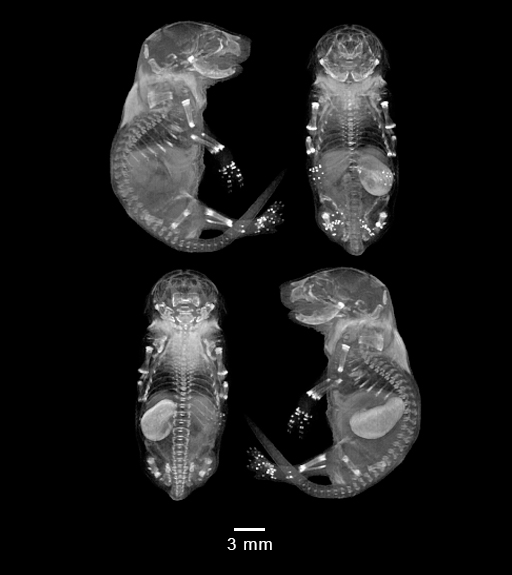

Mouse EmbryoMagnetic Resonance Imaging

Day 19.5 (days post coitum)

MRI Volume Renderings

Sagittal

Coronal

Axial